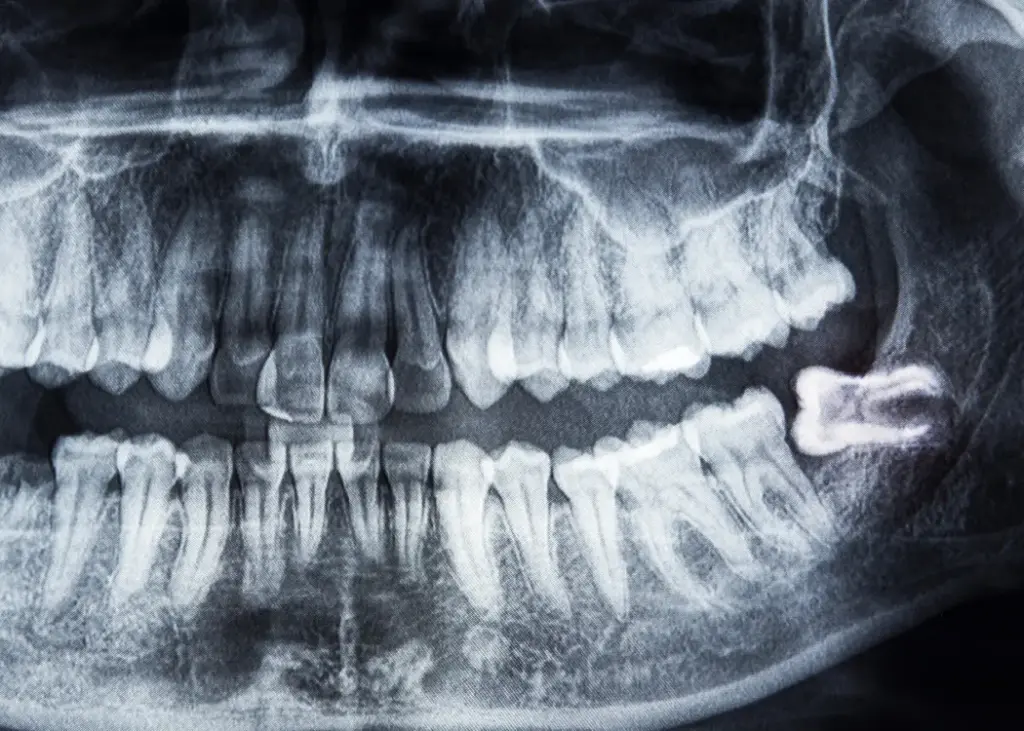

- Evaluation & 3D Imaging: X-rays or scans allow your dentist to assess the position of the wisdom teeth and plan a precise, safe extraction.

- Trapped beneath the bone (impacted)

- At an angle

- Horizontally